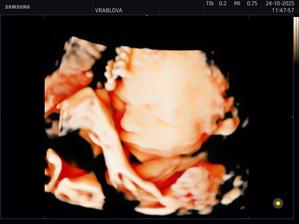

Samko 🩵🤰🏻

Môj vytúžený synček 🥹🩵 už nech ťa mám v náručí 🩵